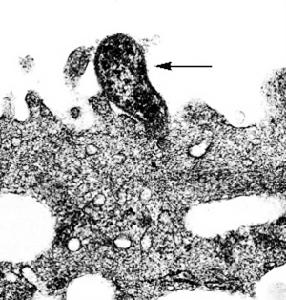

肺炎支原體的一端有一種特殊的末端結構(terminal structure),能使支原體粘附於呼吸道黏膜上皮細胞表面,與致病性有關。

支原體不侵入機體組織與血液,而是在呼吸道或泌尿生殖道上皮細胞粘附並定居後,通過不同機制引起細胞損傷,如獲取細胞膜上的脂質與膽固醇造成膜的損傷,釋放神經(外)毒素、磷酸酶及過氧化氫等。

支原體只能粘附在呼吸道或泌尿生殖道的上皮細胞表面的受體上,而不進入組織和血液。支原體引起細胞損害的原因為:粘附於宿主細胞表面的支原體從細胞吸收營養,從細胞膜獲得脂質和膽固醇,引起細胞損傷;支原體代謝產生的有毒物質,如溶神經支原體能產生神經毒素,引起細胞膜損傷;脲原體含有尿素酶,可以水解尿素產生大量氨,對細胞有毒害作用。支原體除可以粘附於細胞、巨噬細胞表面外,還可以粘附於精子表面,從而阻止精子運動,其產生神經氨酸酶樣物質可干擾精子與卵子的結合。這就是支原體感染引起不育不孕的原因之一。

肺炎支原體 肺炎支原體的致病首先通過其頂端結構粘附在宿主細胞表面,並伸出微管插入胞內吸取營養、損傷細胞膜,繼而釋放出核酸酶、過氧化氫等代謝產生引起細胞的溶解、上皮細胞的腫脹與壞死。誘發機體產生的抗體也可能參與了上述病理損傷。呼吸道分泌的SlgA對再感染有一定防禦作用,但不夠牢固。